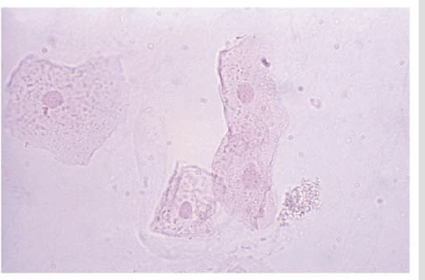

| Clump of squamous epithelial cells | |

| Clump of squamous epithelial cells with folded forms | |